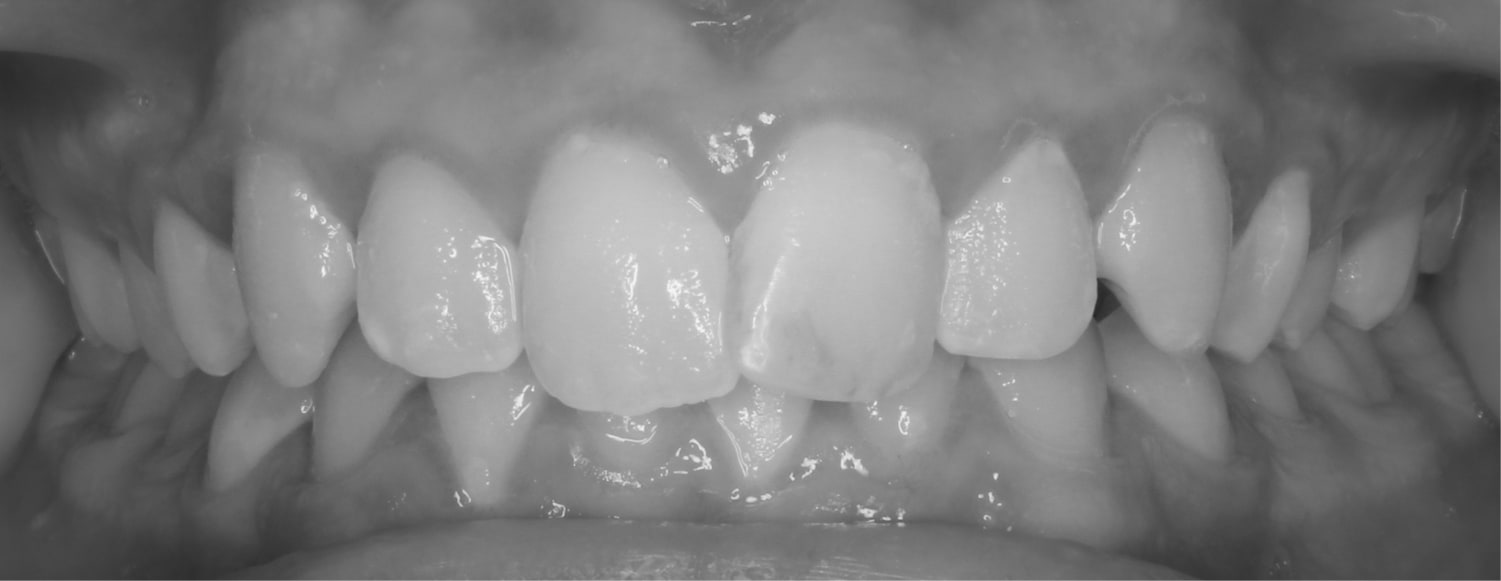

After

Before